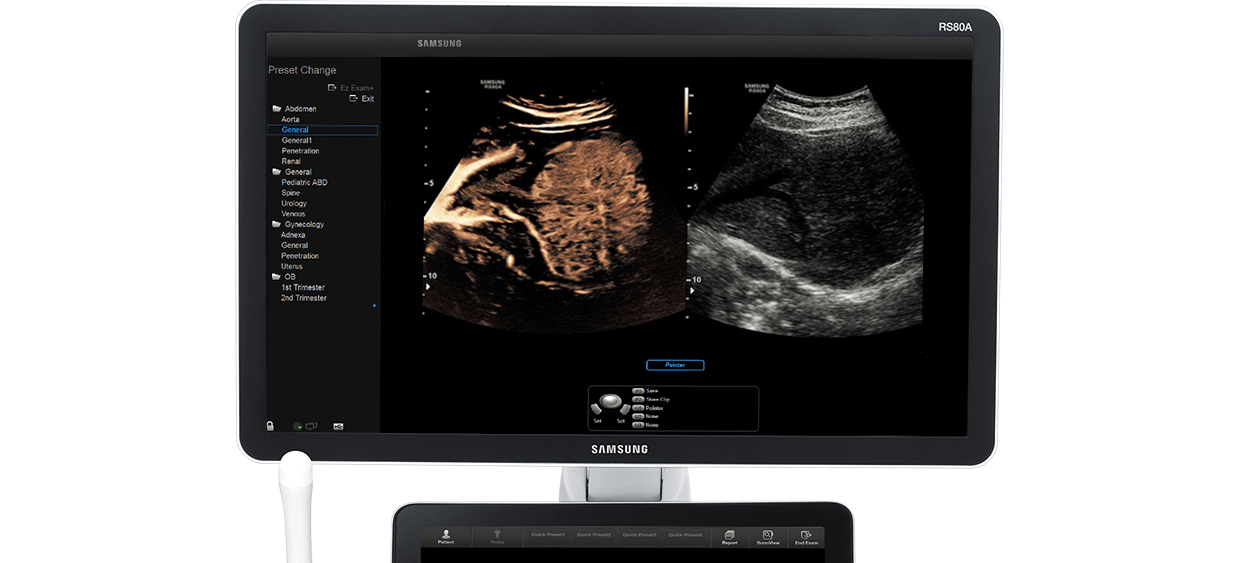

Volume Rendering Technology

RS80A with Prestige

Introducing Samsung's RS80A with Prestige

Volume rendering system with accurate measurement

RS80A with Prestige is Samsung's premium ultrasound system that integrated exquisite image quality and expert tools, empowering professionals to make faster and more confident decisions.